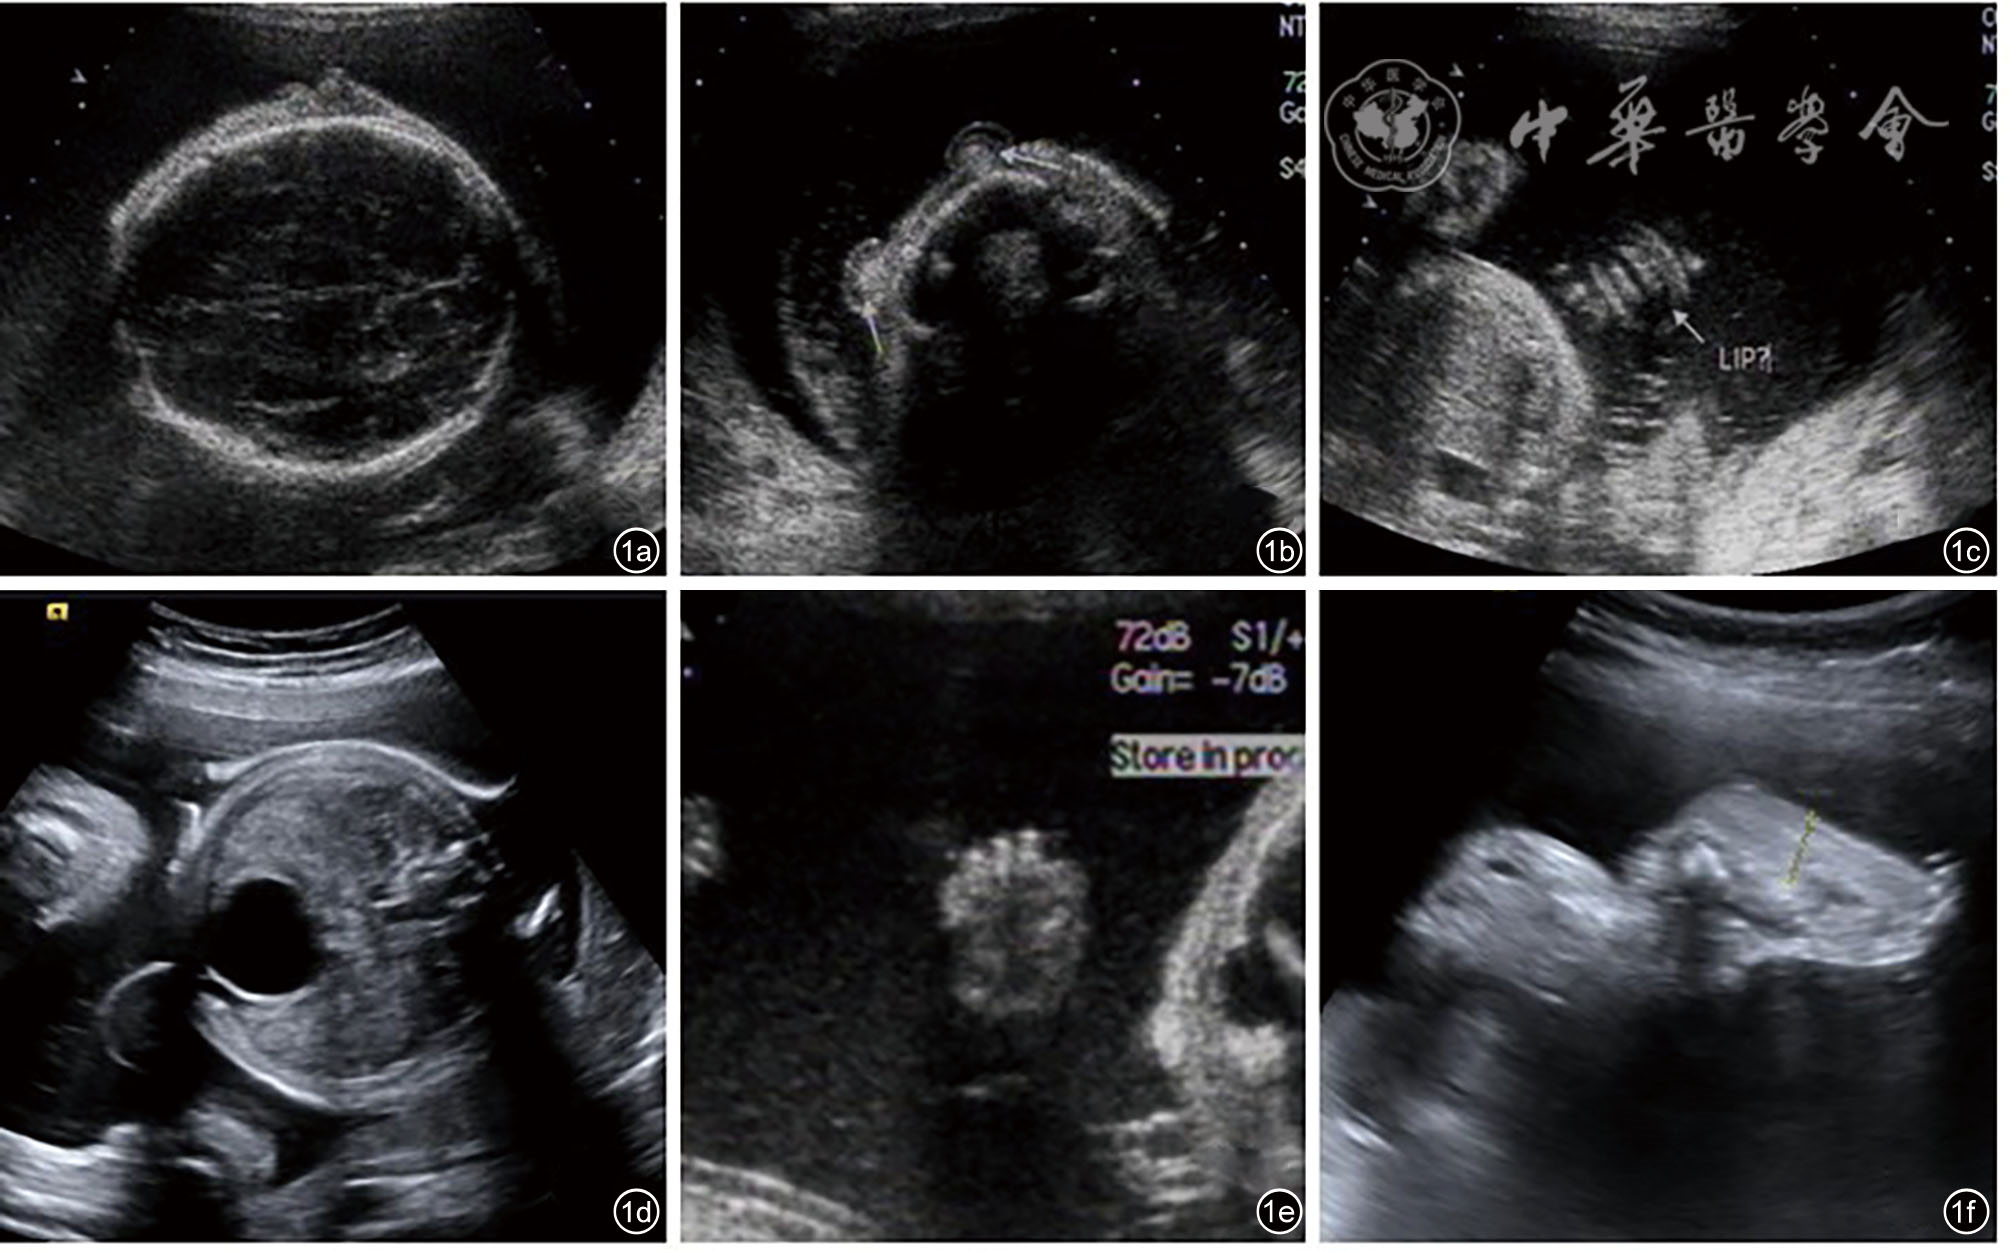

图3 先天性丑角鱼鳞病(病例2)超声及MRI图像。图a为超声图像示孕18+6周胎儿嘴唇稍增厚;图b为超声图像示孕24周胎儿嘴唇增厚外翻;图c为超声图像示孕24周胎儿头皮增厚;图d为超声图像示孕24周胎儿足底皮肤增厚;图e为三维超声显示胎儿嘴唇增厚外翻;图f为MRI显示胎儿头皮及足底皮肤增厚